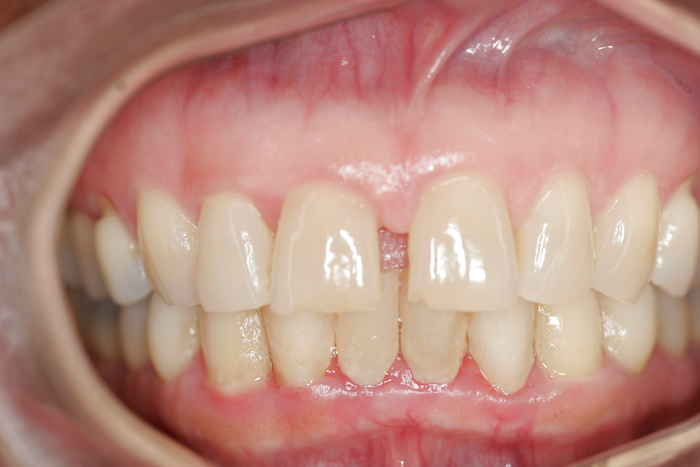

Patient’s teeth three months after surgery and the day the Perio Tray was delivered.